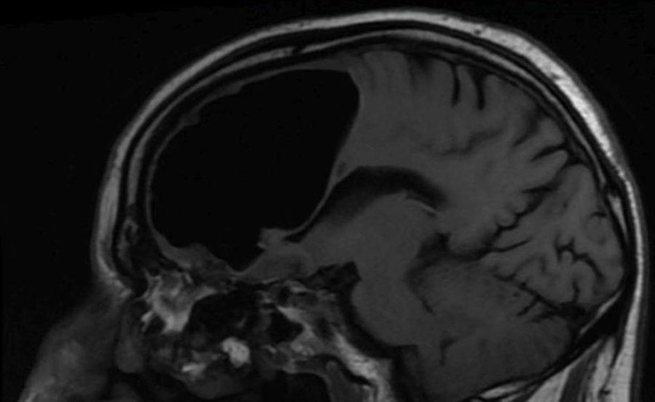

La colpa era di un ictus, sostenevano i medici. Cadute improvvise e debolezza a braccia e gambe ne erano sintomi più che mai evidenti. Eppure si sbagliavano. Niente ictus: il paziente 84enne aveva nel cervello una grande bolla di aria, una tasca di quasi nove centimetri nel lobo frontale destro. Soffriva di pneumocefalo. Vediamo insieme di cosa si tratta.

A riportare il caso clinico è il British Medical Journal Case Reports: la bolla d’aria nel cervello è nota nel campo medico come  pneumocefalo. Non si conoscono praticamente casi simili al mondo o, nel caso, sembrano essere davvero molto rari.

Ma le scansioni del cervello, tramite TAC e MRI, hanno portato alla luce una strana scoperta: non era un ictus, ma una condizione nota come pneumocefalo. Insomma, l’anziano presentava un grande vuoto nel cervello, laddove avrebbe dovuto esserci il lobo frontale destro.

Sembra essere proprio quest’ultimo il caso dell’anziano 84enne. Un piccolo tumore osseo benigno – noto come osteoma – si era formato nei seni paranasali ed era penetrato attraverso la base del cranio, provocando il passaggio dell’aria dal naso alla cavità cranica. La debolezza degli arti era invece dovuta a un piccolo ictus verificatosi nel lobo frontale del paziente, come effetto secondario della compressione della sacca d’aria sul sangue nel cervello.